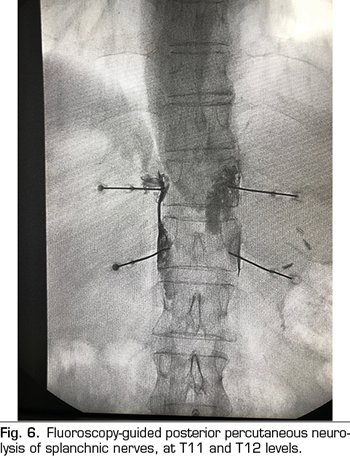

The percutaneous technique is performed using a retrocrural posterior approach, usually guided by fluoroscopy (Figure 6). The lesions can be performed by conventional radiofrequency or using neurolytic agents as in the celiac plexus.